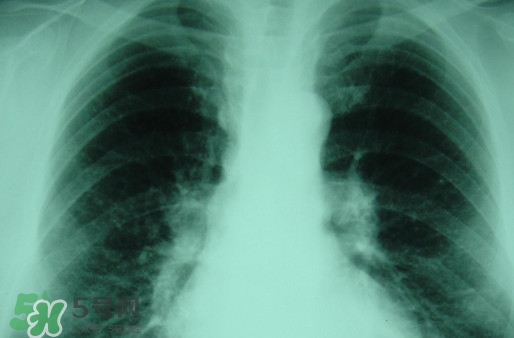

塵肺病多半是因為肺部吸入灰塵導(dǎo)致呼吸不順暢,引發(fā)細(xì)菌感染的病癥,而且隨著近年來塵肺病人得增多及死亡率,國家對此發(fā)布了相關(guān)政策。那么,塵肺病吃什么藥能清肺?塵肺病國家有什么政策?

很多人不知道,其實塵肺病分為無機塵肺和有機塵肺兩種?;颊哂捎谠谌粘5墓ぷ髦兄虚L期吸入生產(chǎn)性粉塵(灰塵),這些粉塵在肺內(nèi)滯留,從而引起的了塵肺病這種全身性疾病,很多人對此認(rèn)識并不清楚。

吸入無機粉塵所致的塵肺,稱為無機塵肺;吸入有機粉塵以后患病被稱為有機塵肺。對早期矽肺療效較好的藥物可以選擇克矽平,有阻止和延緩矽肺進(jìn)展的作用。同時也肯那個會出現(xiàn)發(fā)癢、硬塊,肌肉跳動等不良反應(yīng)。